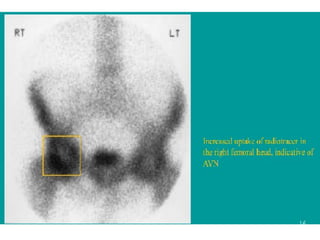

A cold spot within the femoral head is highly

specific for avascular necrosis (AVN) and is the

earliest scintigraphic evidence of this disease.

This finding is usually seen 7-10 days after the

ischemic event.

Over a period of weeks to months, increased

uptake representing revascularization and repair

surrounds and eventually replaces the region of

photopenia.

The central region of photopenia with

surrounding zone of increased uptake is termed

the doughnut sign.

Osteonecrosis

 Initially, uptake is decreased in all phases, which

represents the early ischemic event.

 Later, uptake is decreased within the femoral head in

the perfusion phase and increased around the cold

region in the bone scan phase.

 It represents the reactive zone around the infarcted

segment. The increased uptake from the reparative

zone eventually replaces the photopenic region.